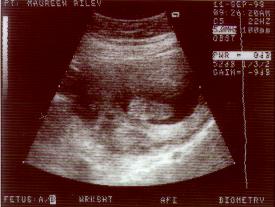

BUT she did come up with this little gem from a quickly turning "Boris":

Yes, you may (or may not) have guessed. That is an image of a 19 week old "foot". That's all you can see in this image! Right there in the middle in that black patch, heel on the right, and toes on the left!

So not exactly the portrait that I expected, but still, pretty cool!